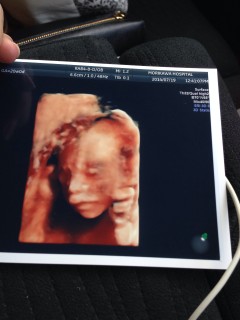

オランダの産院でのエコー写真です。こちらはエコーを頻繁に取ることは胎児に余り良くないと言うことで、20週が最後のエコーになります。最後に性別の男の子とわかり、一緒にエコーを見ていた6歳の息子は「やったー!男だ!」と大喜び。私と主人は「女の子だと思ってたのに~」とちょっとガッカリした1日でした。

左を向いている横顔です。逆子になっていて、性別はわかりませんでした。推定体重は306g。最近胎動が強くなってきました。 鼻ぺちゃは、私似でお兄ちゃんとそっくり(笑)妊娠期間折り返し!会える日を楽しみにしているよ~~~!!

この日は胎児超音波スクリーニング検査をして異常なく3D4Dを両方やりました。 性別は女の子と言われました♡ 男の子希望だったけど4Dで動画を見てたら可愛くて 五体満足健康ならどちらでもよくなっちゃいました♪